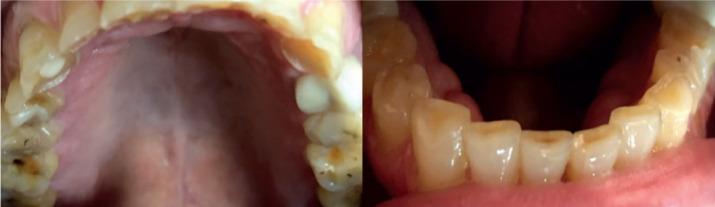

The aim of this study was to assess any bone apposition in the mandibular angle in a group of adult patients diagnosed with bruxism using digital panoramic radiographs.

In the sample of 150 digital panoramic radiographs of 66 women and 84 men with an age range of 24-78 years and diagnosed with bruxism were evaluated.

Among the 300 mandibular angles evaluated, 156 (52%) showed bone apposition against 144 (48%) who did not.

The changes in the mandibular angle, especially bone apposition, can help diagnosing long term bruxism on panoramic radiographs.